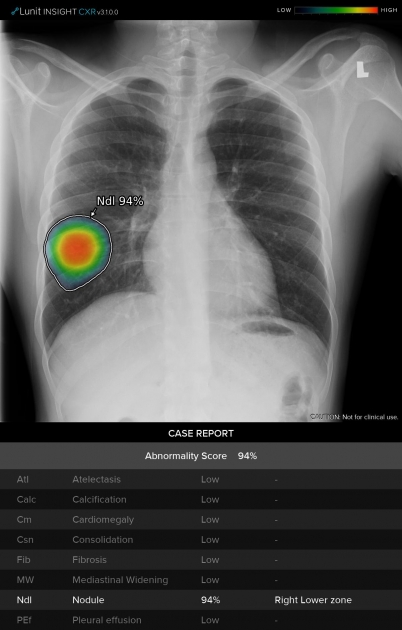

قدمت "جنرال إلكتريك للرعاية الصحية" اليوم "منظومة العناية الصدرية"، وهي مجموعة برمجية من ثماني خوارزميات للذكاء الاصطناعي قائمة على حلول "لونيت إنسايت" لتصوير الصدر بالأشعة السينية، وتساعد في تخفيف المضاعفات السريرية الناجمة عن مرض "كوفيد-19". وتعمل المنظومة المدعومة بالذكاء الاصطناعي على تحليل نتائج التصوير بالأشعة السينية بسرعة وتكشف لأطباء الأشعة وجود أي مظاهر غير طبيعية وتمكنهم من مراجعة النتائج بدقة بما في ذلك احتمال وجود الالتهاب الرئوي، والذي قد يكون دليلاً على احتمال الإصابة بمرض "كوفيد-19"، علاوة على مرض السل والعقيدات الرئوية وغيرها من الأمراض التي تكشفها نتائج التصوير الشعاعي.

وتستفيد "منظومة العناية الصدرية" من قوّة الذكاء الاصطناعي للمساعدة في الحد من هذه الضغوطات من خلال تحليل تلقائي للصور يرصد ثماني نتائج غير طبيعية للتصوير الشعاعي، بما في ذلك الاشتباه بالإصابة بمرض السل والالتهاب الرئوي، وهي أعراض يمكن أن تشير أيضاً إلى الإصابة بمرض "كوفيد-19". وعند قراءة التقرير في أنظمة أرشفة الصور وأنظمة الاتصالات (PACS)، يمكن للمتخصصين في التصوير الشعاعي التعرف بسرعة على حدة الأعراض غير الطبيعية الثمانية المحتملة، وإجراء عملية تركيب الصور، ووصف موقع الإصابة كتابياً بما يثمر في تسريع وتيرة التشخيص والعلاج.

وتوفر "منظومة العناية الصدرية" الدعم الضروري للمساعدة في التعرف بسرعة على الحالات عالية الخطورة بالإضافة إلى مراقبة المرضى الذين يظهرون تطور وتراجع أعراض الجهاز التنفسي الخفيفة. مع معدل دقة يبلغ 97%-99% (المنطقة تحت المنحنى AUC)، وتم تخصيص الخوارزميات الفعالة التي تدعم تقنيات الذكاء الاصطناعي لاكتشاف نتائج الفحوص الإشعاعية في غضون ثوان معدود ة. وفي إحدى الدراسات، أظهرت النتائج انخفاضاً بنسبة 34٪ في وقت القراءة لكل حالة مرضية.

وإضافة إلى الكشف عن الالتهاب الرئوي، تدعم "منظومة العناية الصدرية" أمراضاً مثل السل؛ وانخماص الرئة؛ والتكلس؛ وتضخم القلب؛  والتليف؛ واتساع المنصف؛ والعقيدات الرئوية؛ وكشف الانصباب الجنبي.